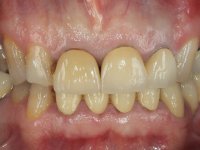

O paciente não gostava do aspeto “artificial” dos seus dentes.

Paciente do sexo masculino, com 42 anos de idade, não fumador. Apresentava uma reabilitação metalo -cerâmica feita há mais de 10 anos com exposições radiculares e infiltrações. No maxilar superior apresentava uma coroa no 1.1,uma ponte de dois elementos no 2.1 e 2.2.e uma ponte de 4 elementos nos dentes 2.4,2.5,2.6 e 2.7 com o 2.6 como pôntico. Os dentes 1.6/1.5/1.4/1.3/1.2/1.1/2.1/2.2/2.3/2.4/2.5 e 2.7 apresentam tratamento endodôntico radical com o 2.4/2.5 e 2.7 a necessitarem de ser refeitos. No maxilar inferior apresentava uma ponte metalo-cerâmica de 4 elementos nos 4 incisivos e uma ponte de 3 elementos (3.3 e 3.4) com um dente supranumerário como pôntico. Os dentes 4.6/4.5 e 4.2 apresentavam tratamento endodôntico com o 4.2 a necessitar de ser refeito. Os dentes 4.3 e 4.4 apresentavam extensas cáries linguais com algum comprometimento mesial. As peças protéticas apresentavam-se infiltradas com exposição radicular associada. Apresentava uma D.V.O. diminuída e uma mordida cruzada lado direito. O paciente tinha uma satisfatória saúde periodontal e uma boa higiene oral.

Foi proposto ao paciente fazer uma reabilitação total com infraestruturas em zircónia revestidas a cerâmica. No maxilar superior, seriam realizadas 6 coroas (1.3/1.2/1.1/2.1/2.2/2.3), uma ponte de 3 elementos (1.4/1.5/1.6) e uma ponte de 4 elementos (2.4/2.5/2.6 e 2.7). No maxilar inferior, foram propostas 7 coroas (4.3/4.2/4.1/3.1/3.2/3.5 /3.6) e duas pontes (4.4//4.5/4.6) e (3.3/3.4#/3.4).O objetivo seria subir a D.V.O., descruzar a mordida do lado direito, eliminar as infiltrações e as exposições radiculares e reabilitar o paciente com estruturas protéticas com aspeto mais natural.

A primeira acção terapêutica foi tentar melhorar o tratamento endodôntico dos dentes (2.4/2.5/4.2)). A sua manutenção em boca seria condicionada pelo sucesso desta intervenção. Seguidamente foram feitas impressões em alginato e registo inter-maxilar em silicone para confeção em laboratório de uma ponte provisória em acrílico com reforço. O objetivo desta ponte provisória seria ensaiar o aumento da D.V.O. e descruzar a mordida do lado direito. Foi utilizado um monobloco de 13 dentes com o dente 2.6 com o pôntico. As coroas e as pontes foram removidas e os remanescentes coronários foram repreparados. A ponte provisória foi rebasada primeiramente com acrílico auto-polimerizável e de seguida com resina composta. Após 2 semanas de permanência em boca, foram feitas as impressões para confeção da ponte provisória inferior também realizada em laboratório. Especial cuidado foi colocado na remoção das coroas antigas, sendo feito primeiramente um corte axial que permitiu que fossem removidas de uma forma menos traumática. A temporização foi feita durante 8 semanas, permitindo que os tecidos gengivais estabilizassem posicionalmente. As impressões definitivas foram realizadas após afastamento gengival utilizando a técnica do fio único impregnado. Foi utilizada a técnica de dupla mistura com dupla viscosidade (putty soft e light).Simultaneamente foi realizada a recolha das relações inter-maxilares e o registo com arco facial. Foram confecçionados os modelos de trabalho e feita a sua correta montagem em articulador semi-ajustável. Em seguida foram feitas infra estruturas em zircónia que posteriormente foram revestidas por cerâmica. A prova de “biscoito” foi realizada em boca para avaliação estética e funcional sendo também avaliado o seu assentamento e ajuste. A reabilitação definitiva foi cimentada em boca utilizando um cimento de ionómero de vidro reforçado por resina.